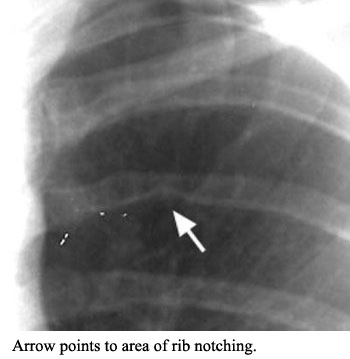

A twenty-three year old female presents to your clinic with complaints of being easily tired, pain in her lower extremities with weakness and cold feet, an inability to tolerate vigorous exercise, frequent headaches, and epistaxis (nosebleed). The patient reports these are not new symptoms, but have occurred over a number of years and have recently increased in their incidence. On physical exam you find: cool lower extremities with an absence of distal pulses and diminished femoral pulses, the blood pressure in the upper extremities is elevated (190/100), while the blood pressure in the lower extremities is 40/10; a systolic murmur is heard over the 5th left intercostal space which radiates to the interscapular region. A chest x-ray is performed and significant rib notching is noted along with a visible dilation of the aorta in the region of the aortic knob. The patient is diagnosed with coarctation of the aorta based on physical exam and findings.

Pre- and post-coarctation dilation was seen in the region of the aortic knob. There was also rib notching, which reflects the erosion of bone by intercostal arteries that have become dilated and tortuous by the great volume of blood they are carrying as collateral blood flow.